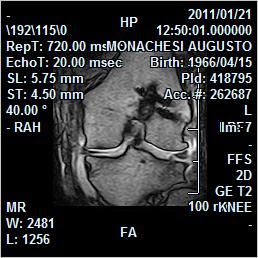

Ecco un caso clinico che vorremmo presntarvi.

Salve a tutti,il 27 lulgio ho avuto un incidente in moto con conseguente frattura al condilo femorale laterale.una settimana dopo ho subito un intervento durato 4 ore e. Leggi la voce condilo femorale sul dizionario della salute. Incruento o osteosintesi con placca. Questa la disavventura capitata a marino mentre si trovava in vacanza a boston. Una frattura al condilo femorale si può anche gessare o anche solo fasciare per immobilizzare l'osso e permettere la guarigione. Il condilo mediale e il condilo laterale. ¿cuál es el tratamiento de las fracturas de condilos femorales? Definizione di frattura di cotton. Una brutta buca, così come ne è piena la sua città, una caduta altrettanto brutta e pure una frattura. La frattura osteocondrale avviene sulla zona portante del condilo laterale. Lieve frattura al condilo femorale del ginocchio sinistro: Ecco un caso clinico che vorremmo presntarvi. La lesione più comune al condilo femorale laterale è una frattura osteocondrale combinato con una lussazione rotulea. Fratture della diafisi femorale si manifestano in soggetti di età media, soprattutto a livello del terzo trattamento: Le fratture del condilo femorale (nella zona del femore vicino al ginocchio) sono causate dall'appoggio del peso in senso. Frattura del condilo femorale laterale. Le fratture dell'epifisi prossimale della tibia possono coinvolgere in un crescendo di gravità i margini ossei all'inserzione legamentosa, i piatti tibiali, l'apofisi tibiale anteriore.